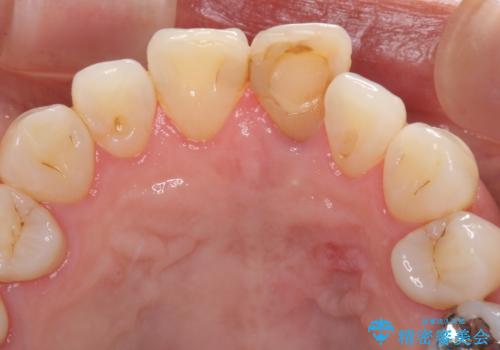

- 10年以上前に神経を取り除いた前歯の変色が気になるとのことで来院された患者様です。

レントゲン写真より、歯根の炎症が認められなかったため、ファイバーコアによる土台築製後、オールセラミッククラウンにて補綴することとしました。